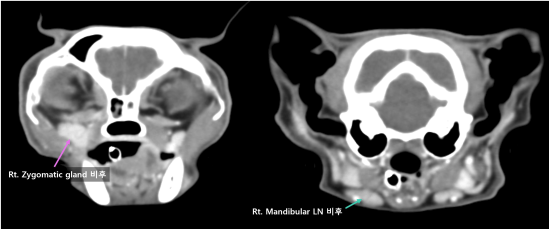

정확한 환자 상태 평가 및 확정진단을 위하여 전신 CT 촬영 및 조직 검사를 계획하였습니다.

고양이 구강 SCC 내원 당시 CT 검사 2 / 출처: 에스동물암센터

📌CT 검사 결과

이번 영상 검사에서 확인된 병변은 위턱뼈(상악)에서 시작된 병변일 가능성이 가장 높습니다. 뼈가 녹아내리는 모습(bone lysis)과 뼈 표면이 반응하는 소견(periosteal reaction)이 보여, 악성 종양일 가능성을 우선적으로 고려해야 합니다.

다만, 코(비강)에서 시작된 병변이 위턱뼈로 퍼진 것일 가능성도 완전히 배제할 수는 없습니다. 따라서 정확한 원인을 알기 위해서는 조직 검사가 필요합니다.

02 조직 검사 결과

환자는 비강 유래 종양보다는 구강 상악 유래 종양의 비강 및 안와 침범이 의심되었으며, 유의적인 전이 소견이 뚜렷하게 확인되지 않았습니다.